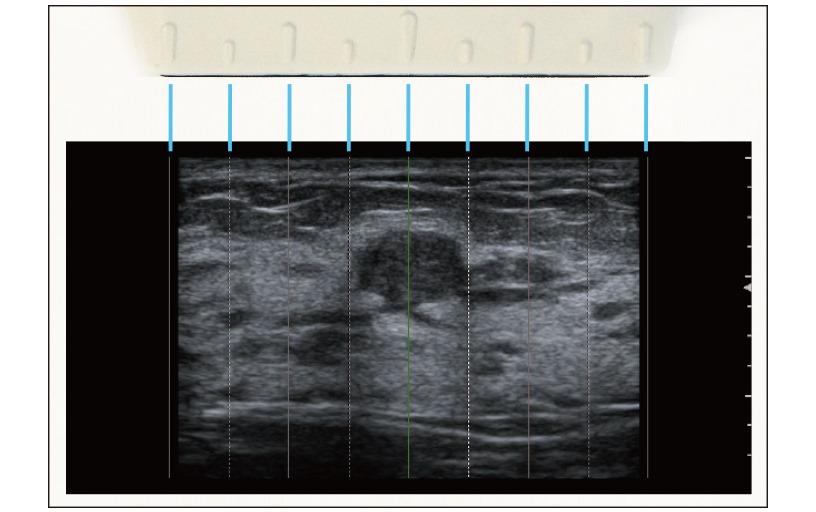

Imágenes compuestas, Mejora la visualización de los límites del tejido al transmitir haces en varias direcciones, reduciendo los artefactos que suelen producirse al utilizar una trayectoria de haz única.

ANR (Reducción acústica de ruido), Analiza la señal recibida de cada canal en tiempo real y suprime las señales que perturban la imagen.